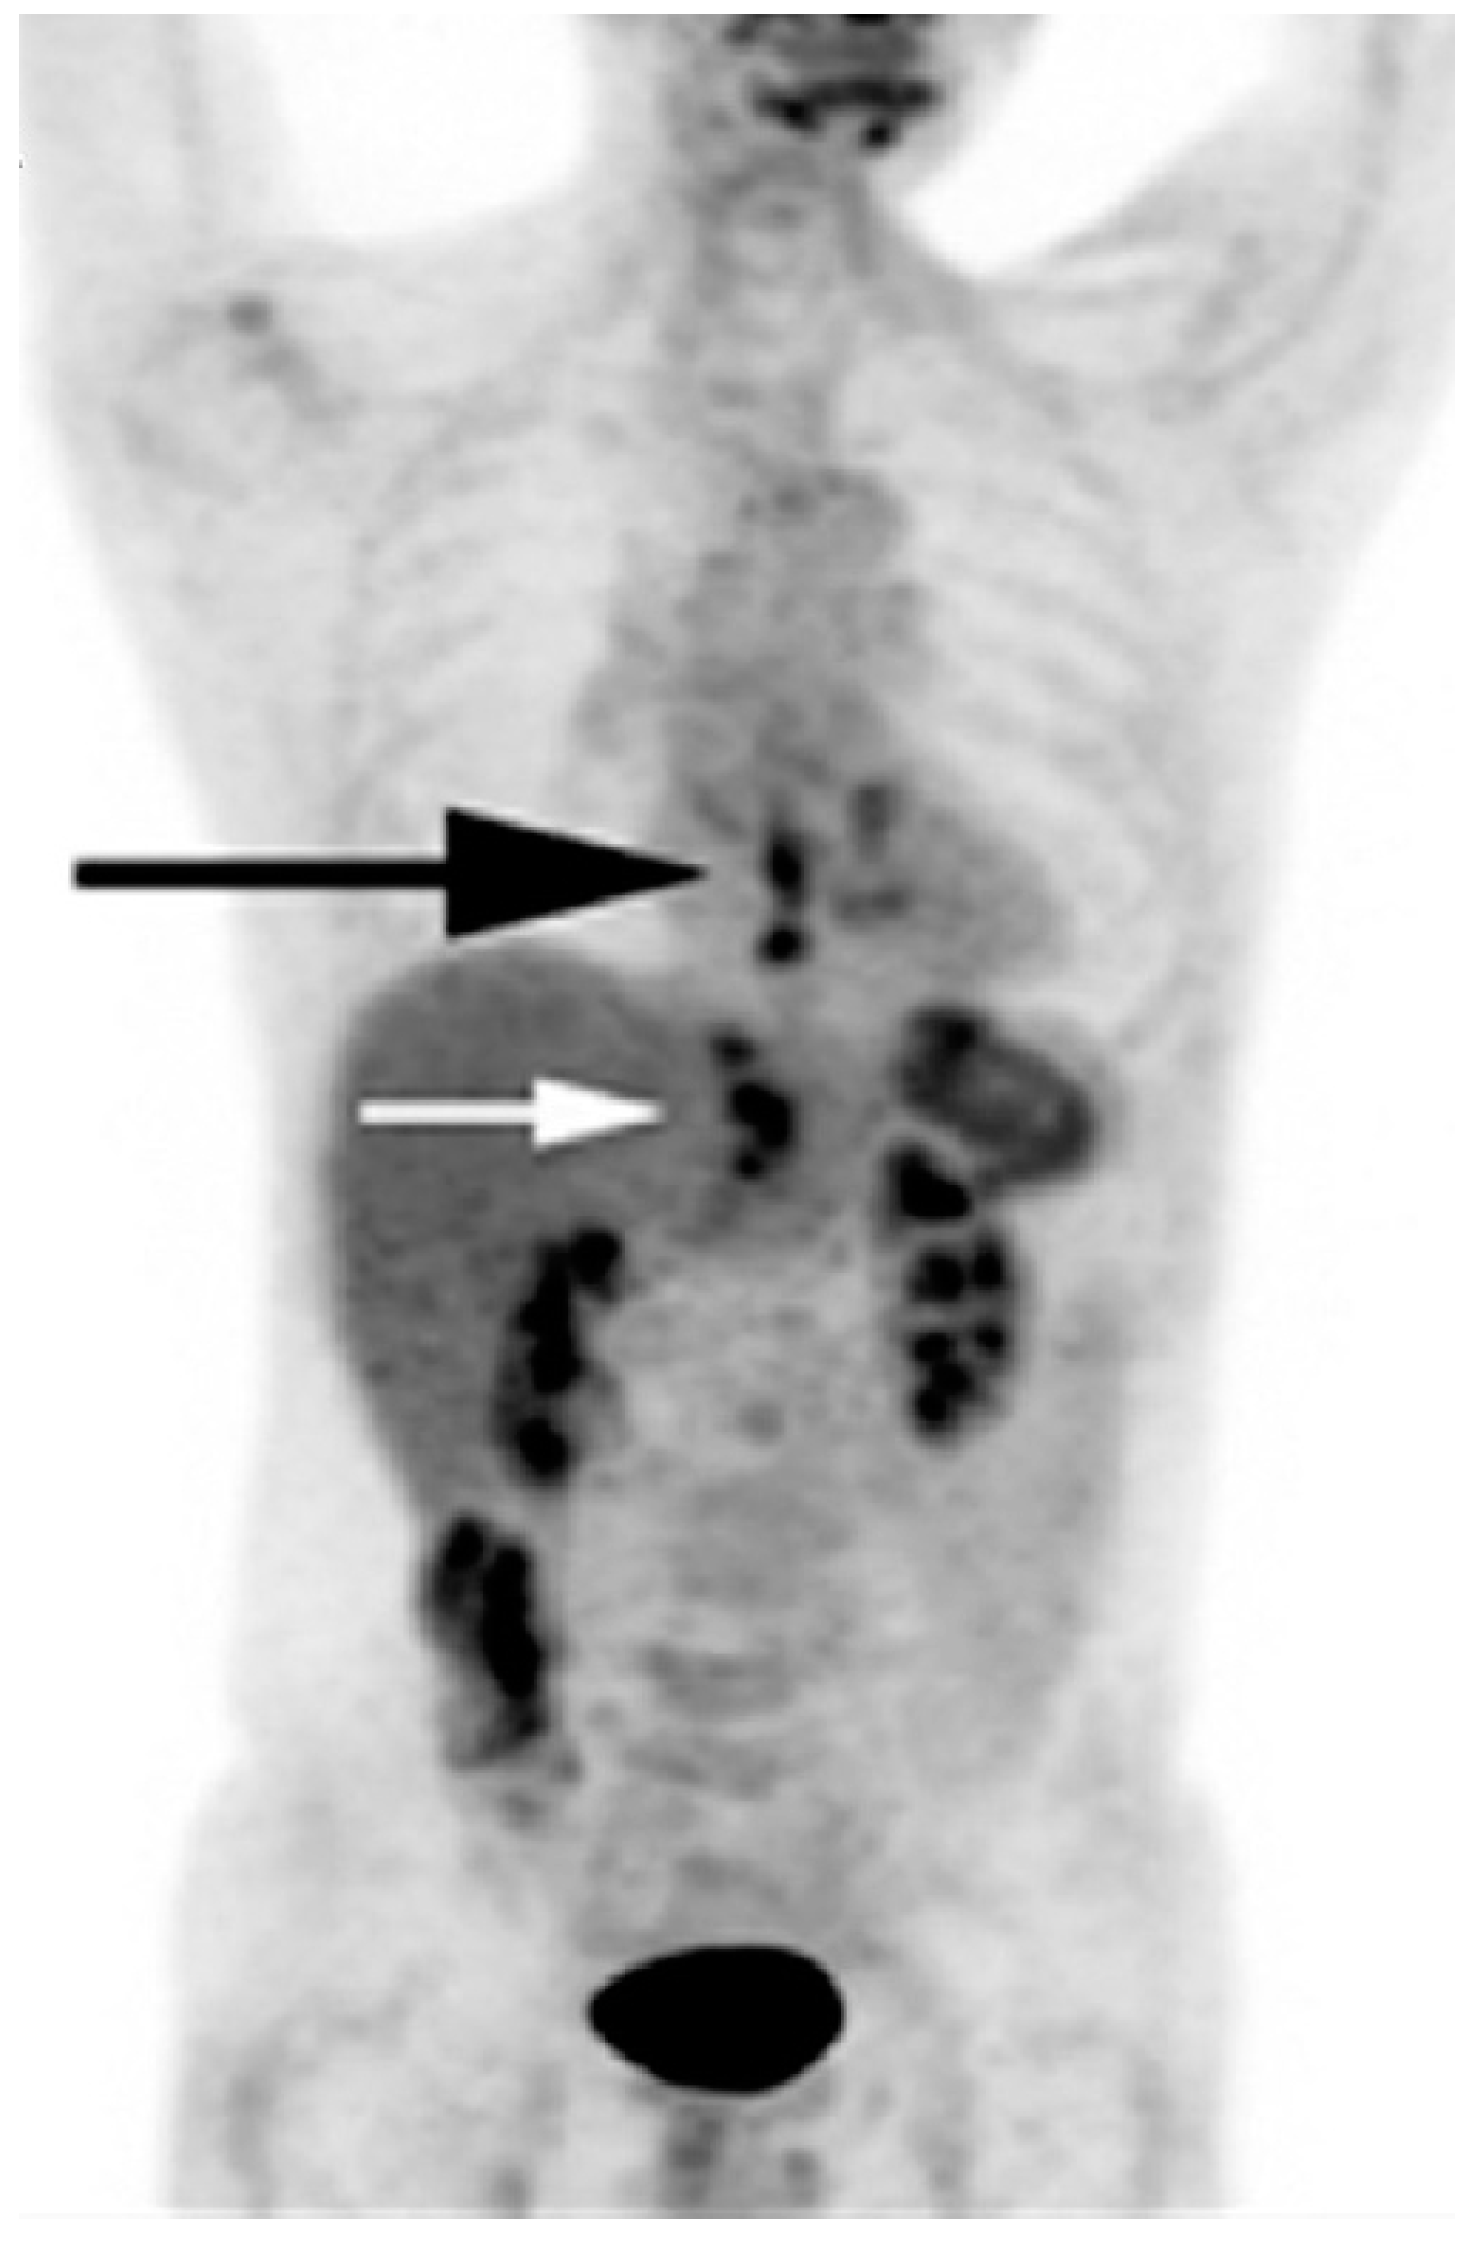

- Kumar, K.; Singh, H.; Gupta, R.K.; Bal, C.; Kumar, R. Erlotinib-induced cutaneous toxicity: Findings on 18F-FDG PET/CT imaging. Clin. Nucl. Med. 2015, 40, e251–e252. [Google Scholar] [CrossRef] [PubMed]

- Martinez-Rodriguez, I.; Garcia-Castano, A.; Quirce, R.; Jimenez-Bonilla, J.; Banzo, I. Erythema nodosum-like panniculitis as a false positive 18F-FDG PET/CT in advanced melanoma treated with dabrafenib and trametinib. Clin. Nucl. Med. 2017, 42, 44–46. [Google Scholar] [CrossRef] [PubMed]